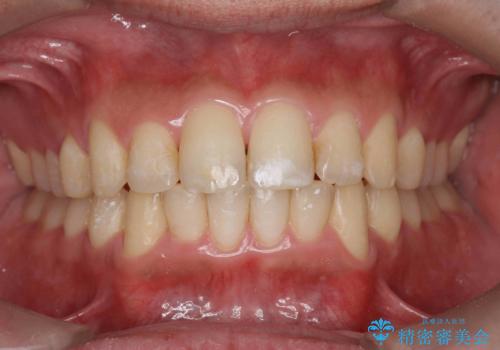

ワイヤーによる全体的ながたつきの矯正治療